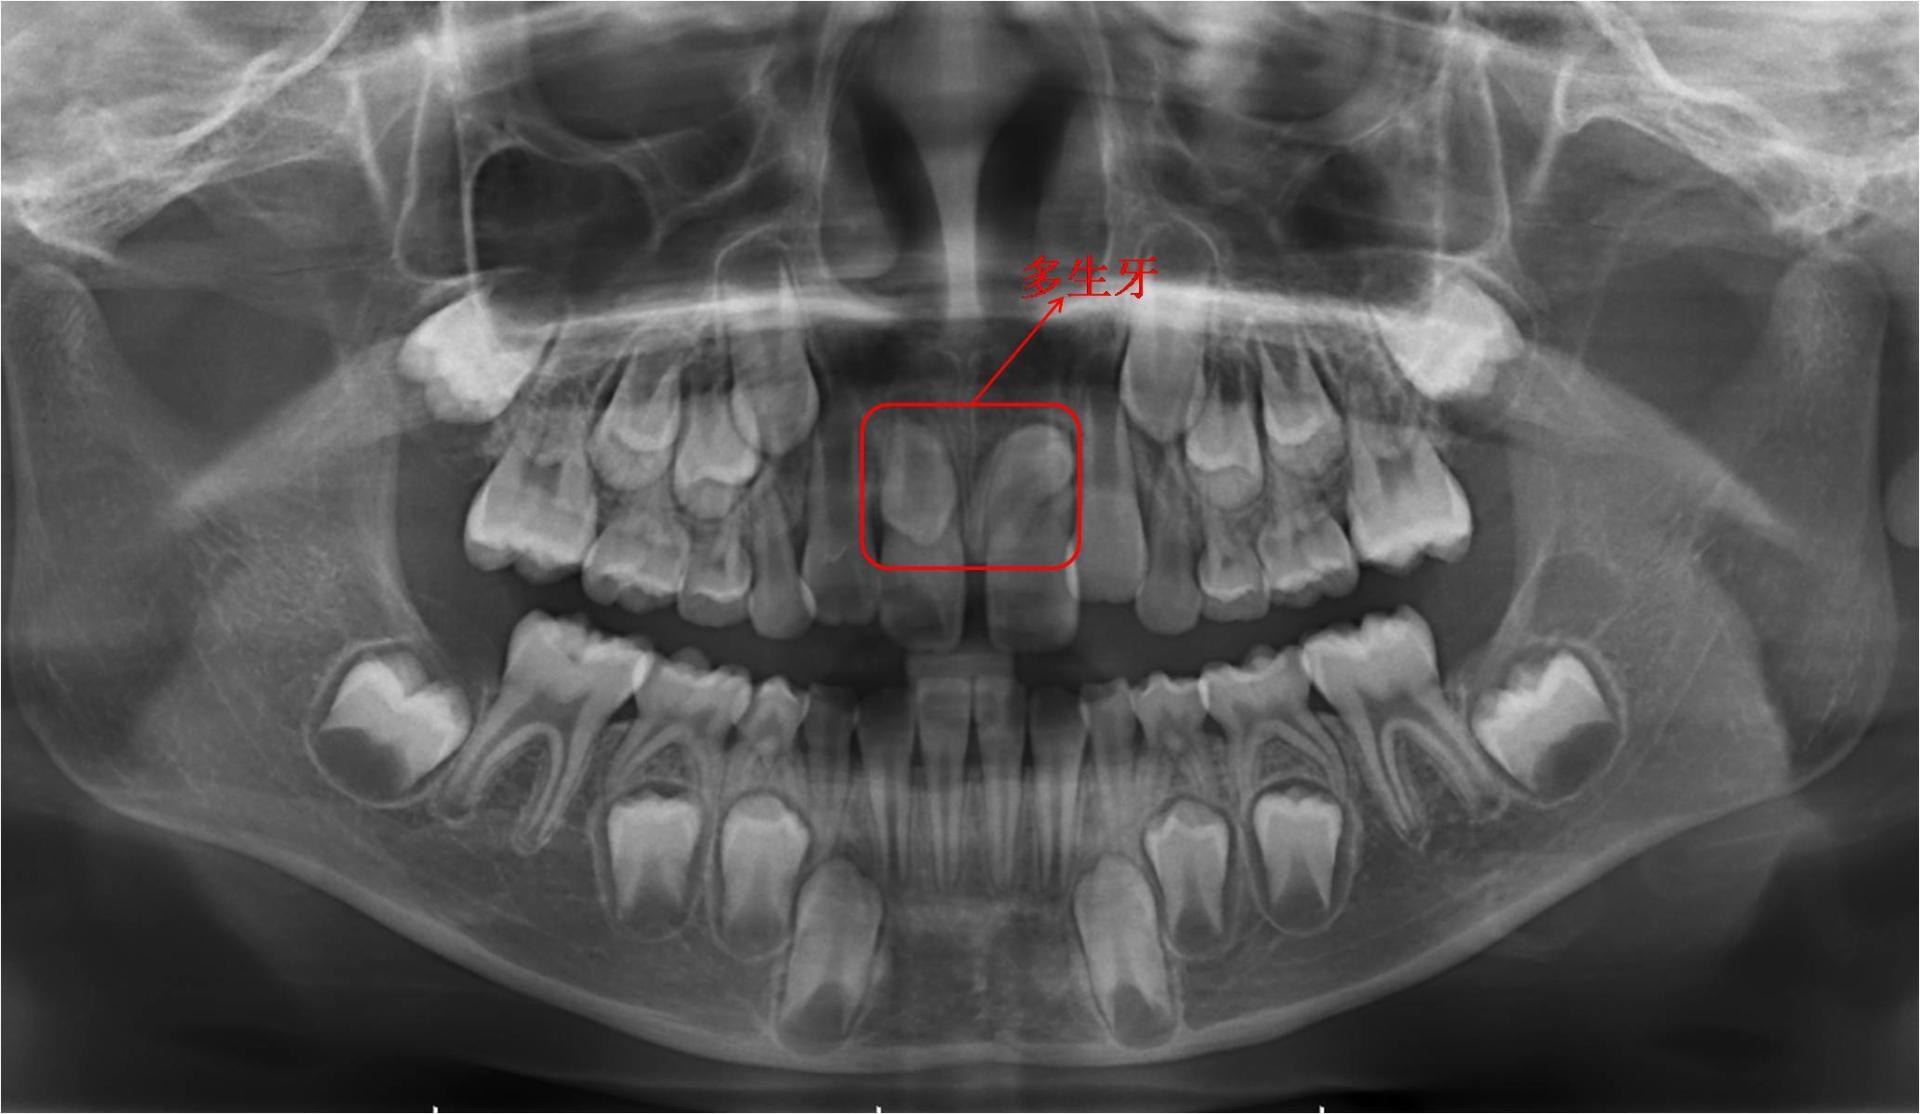

4、多生牙

有时会在两颗正常的恒牙胚间长一到两颗多生牙,多生牙不但会影响正常恒牙的顺利萌出,而且存在时间过长则易形成含牙囊肿,需及时拔除后,以便让恒牙萌出。